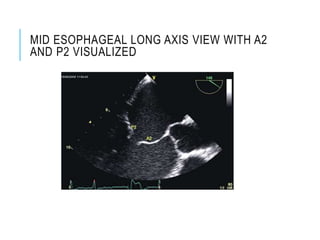

MID ESOPHAGEAL LONG AXIS VIEW WITH A2

AND P2 VISUALIZED

MID ESOPHAGEAL LONGAXIS VIEW WITH A2 AND P2 VISUALIZED